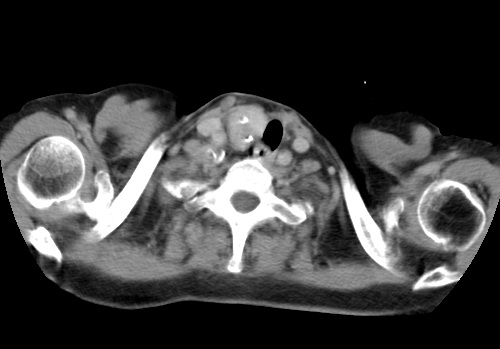

标题: CT23982:女67岁,胸部扫描时发现,甲状腺瘤? [打印本页]

标题: CT23982:女67岁,胸部扫描时发现,甲状腺瘤?

右侧甲状腺腺瘤!支持!不排除甲状腺癌可能!建议手术切除!

右侧甲状腺占位性病变,性质待定(甲状腺腺瘤?);建议:必要时行进一步检查。

右侧甲状腺占位性病变,性质待定(甲状腺腺瘤?);建议穿刺活检。

右侧甲状腺占位性病变,甲状腺腺瘤可能,建议穿刺活检。